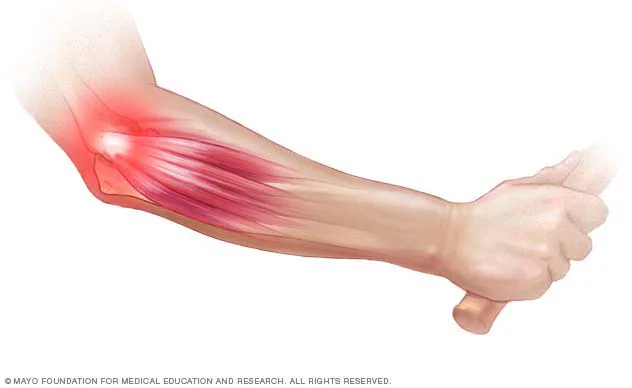

Në Fizio Tirana, ne ofrojmë trajtim të specializuar për bërrylin e tenisit (epikondiliti lateral), një problem shumë i zakonshëm që shkakton dhimbje në pjesën e jashtme të bërrylit dhe ndikon drejtpërdrejt në aktivitetet e përditshme dhe sportive.

Çfarë është Bërryli i Tenisit?

Bërryli i tenisit është një inflamacion ose dëmtim i tendinave që lidhen me muskujt e parakrahut në pjesën e jashtme të bërrylit. Ky problem nuk prek vetëm sportistët, por edhe persona që bëjnë lëvizje të përsëritura si:

Problemet e tilla lidhen shpesh me inflamacion dhe dëmtime të indeve, të ngjashme me gjendje si bursiti, ku inflamacioni shkakton dhimbje dhe kufizim të lëvizjes

Simptomat Kryesore

Pacientët me bërryl tenisi zakonisht përjetojnë:

- Dhimbje në pjesën e jashtme të bërrylit

- Dhimbje gjatë kapjes së objekteve

- Dobësi në dorë

- Vështirësi në aktivitete të thjeshta (mbajtja e gotës, hapja e derës)

- Dhimbje që përhapet drejt parakrahut